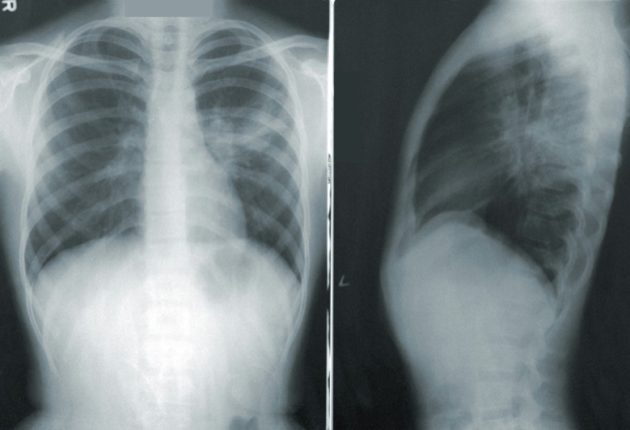

Depuis 2024, près de 1000 personnes à risque participent à ce programme vaudois mené par Unisanté et le CHUV. Il s’adresse aux 50–79 ans ayant un lourd passé tabagique. Chaque participant bénéficie d’un scanner thoracique annuel à faible dose, permettant de repérer précocement des nodules pulmonaires susceptibles de correspondre aux premiers stades de la maladie.

Dans 10 à 15 % des cas, une anomalie est détectée, le plus souvent surveillée par imagerie. Seule une minorité nécessite des examens plus invasifs. Ce suivi permet surtout d’identifier des cancers à un stade précoce, moment où la chirurgie et la guérison restent possibles.